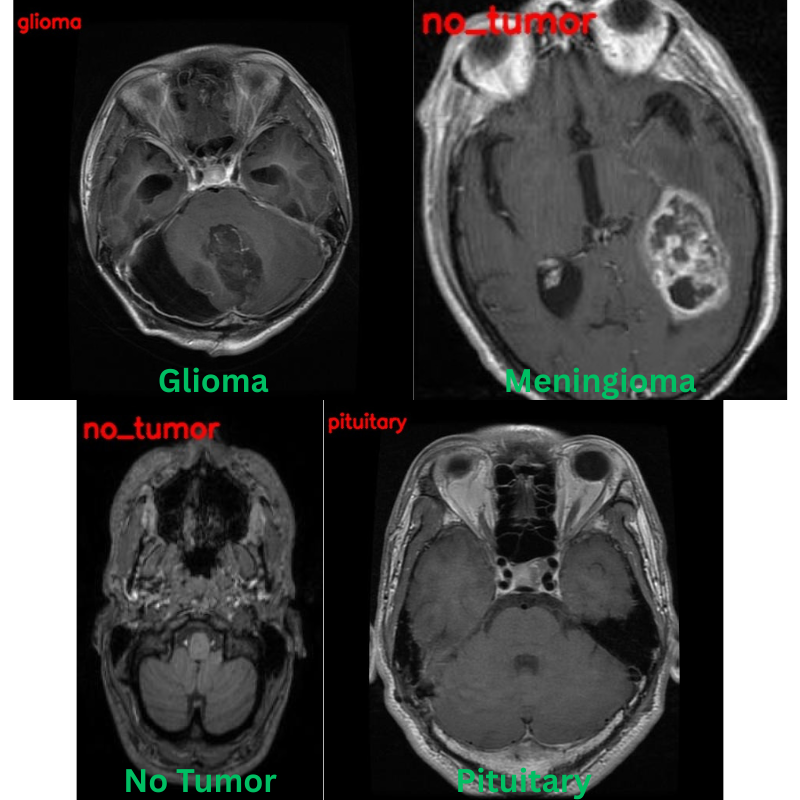

There are two subdirectories, and we will focus on the classification_task one. As we can see, the dataset contains four classes: Glioma, Meningioma, Pituitary Tumor, and No Tumor.

Following are some of the samples from the dataset.

The following are the results. The red text represents the predictions and the green text the ground truth labels.

Apart from one image, that is meningioma predicted as no_tumor, the other three predictions are correct.